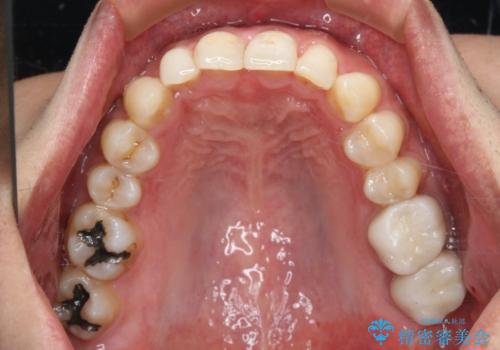

- 右上下6番の銀歯のやり変えを希望された患者様です。

切削量・形態を考慮し、上はセラミッククラウン、下はセラミックインレーでの治療を選択しました。

上はう蝕が歯頚部まで達していたのでクラウンでの治療を選択しました。

銀歯直下もう蝕が進行していたので全て除去した上でCRにて裏層しています。

下はクラウンほど切削量が多くないと判断し、インレーでの治療を選択しました。